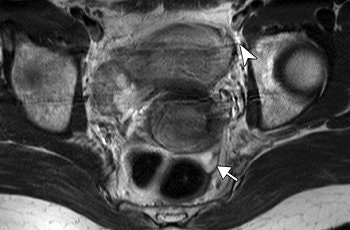

| A 48-year-old woman with true-positive left internal iliac lymph node metastasis in stage IIB uterine cervical cancer. MR axial T2-weighted fast spin-echo image (TR/TE, 5,000/68; echo-train length, 21) shows ovoid lymph node (arrow, 10-mm short-axis diameter) with smooth margin in left internal iliac area. |

According to the results, MRI showed 86 lymph nodes in total and histopathology revealed 17 metastatic lymph nodes in 55 patients. The authors found that the mean short-axis diameter of metastatic lymph nodes was larger than that of nonmetastatic lymph nodes. The sensitivity of this MR criterion was 33.3% and the accuracy was 91.4%.

"The prediction of nodal status was most accurate when a size criterion of greater than 9 mm was applied to the short-axis diameter of the lymph node," the group wrote.